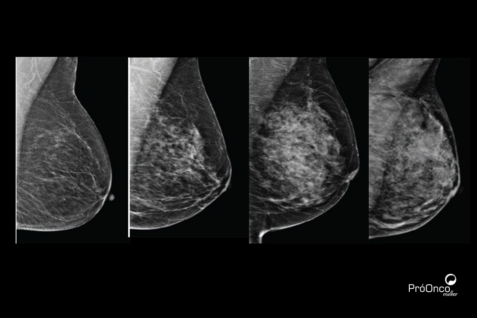

Classificação BI-RADS: o que significa cada categoria?

O BI-RADS, sigla para Breast Imaging Reporting and Data System, é um sistema internacional criado para padronizar os laudos dos exames de imagem das mamas, como mamografia, ultrassonografia e ressonância magnética. Ele orienta os médicos sobre a conduta mais adequada e facilita a comunicação dos resultados, sempre com o objetivo de garantir um acompanhamento seguro e responsável.

Agora, vamos entender o que significa cada uma das classificações?

BI-RADS 0 – Exame inconclusivo

Quando o laudo indica BI-RADS 0 significa que o exame ainda não foi conclusivo. Nesses casos, pode ser necessária a realização de exames complementares ou a comparação com imagens anteriores. Essa categoria não indica doença, apenas a necessidade de mais informações para uma avaliação correta.

BI-RADS 1 – Exame normal

O BI-RADS 1 corresponde a um exame dentro da normalidade. Não há achados suspeitos, e o acompanhamento segue conforme a rotina indicada pelo médico.

BI-RADS 2 – Achados benignos

Já o BI-RADS 2 aponta alterações benignas, como cistos simples ou calcificações sem risco. Apesar de aparecerem no exame, essas alterações não representam câncer e também não exigem mudanças no acompanhamento habitual.

BI-RADS 3 – Provavelmente benigno

Na categoria BI-RADS 3, o exame mostra uma alteração que tem alta probabilidade de ser benigna, mas que precisa ser observada com mais atenção ao longo do tempo. Por isso, é comum que o médico recomende repetir o exame em um intervalo menor, geralmente em torno de seis meses, para garantir que não haja mudanças.

BI-RADS 4 – Achado suspeito

O BI-RADS 4 indica um achado suspeito que merece investigação mais aprofundada. Nessa situação, o exame de imagem não permite afirmar se a alteração é benigna ou maligna, e a biópsia costuma ser indicada para esclarecimento diagnóstico. Essa categoria pode ser subdividida em níveis de suspeição, algo que será avaliado individualmente pela equipe médica.

BI-RADS 5 – Altamente sugestivo de malignidade

Quando o resultado é BI-RADS 5, os achados apresentam características fortemente sugestivas de câncer de mama. A investigação precisa ser rápida e cuidadosa, e a confirmação do diagnóstico é feita por meio de biópsia. Embora esse resultado gere um grande impacto emocional, o diagnóstico precoce amplia significativamente as possibilidades de tratamento e bons resultados.

BI-RADS 6 – Câncer já confirmado

Por fim, o BI-RADS 6 é utilizado quando o câncer de mama já foi confirmado anteriormente por biópsia. Nesses casos, os exames de imagem ajudam a avaliar a extensão da doença, orientar o planejamento do tratamento e acompanhar a resposta às terapias indicadas.